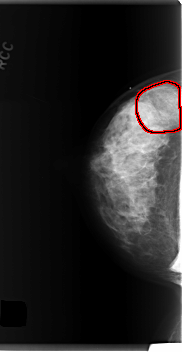

C_0279_1.RIGHT_CC

RIGHT_CC LINES 5976 PIXELS_PER_LINE 3080 BITS_PER_PIXEL 12 RESOLUTION 50 OVERLAY

FILE: C_0279_1.RIGHT_CC.OVERLAY

TOTAL_ABNORMALITIES 1

ABNORMALITY 1

LESION_TYPE MASS SHAPE OVAL MARGINS OBSCURED

ASSESSMENT 4

SUBTLETY 4

PATHOLOGY BENIGN

TOTAL_OUTLINES 1

BOUNDARY